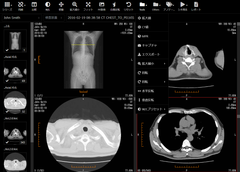

ビューア画面3

3. Webブラウザで動作する高速なビューア

ビューアはWebブラウザ(Google ChromeやFirefox)上で動作するので、クライアント端末に新たにソフトウェアをインストールする必要がありません。ネットワーク内のどの端末からでも、WebブラウザからURLにアクセスしてログインするだけで画像を閲覧できます。CTやPETなどの大量の画像が含まれる検査もスピーディに表示することができます。